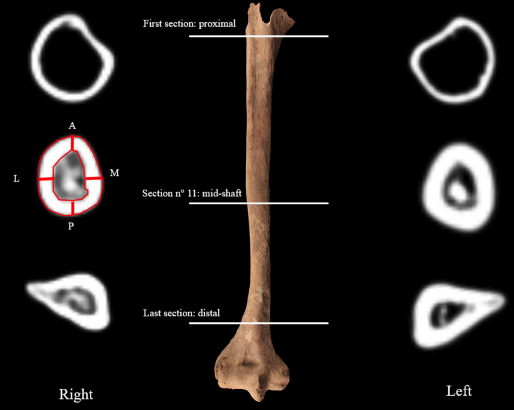

Обнаруженная находка относится к VI-VIII векам. Возраст мужчины на момент смерти составлял 40-50 лет, его рука была ампутирована в районе середины предплечья. Предположительно, руку пришлось удались из-за травмы, а вместо нее мужчина использовал протез, заканчивавшийся ножом.

Осмотр останков также показал, что зубы мужчины были сильно стерты — вероятно, он регулярно закреплял с их помощью протез. Также на кладбище были найдены останки обезглавленной лошади, нескольких собак и сотен других людей.